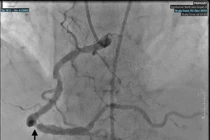

Hình ảnh: Động mạch vành phải được tái thông sau khi đặt stent - Ảnh BVCC

Kết quả chụp cho thấy tổn thương hẹp tại động mạch vành phải đã tiến triển, trong khi các stent cũ vẫn thông tốt, không bị tái hẹp. Trên cơ sở đó, các bác sĩ đã quyết định đặt thêm 01 stent mới tại vị trí tổn thương.